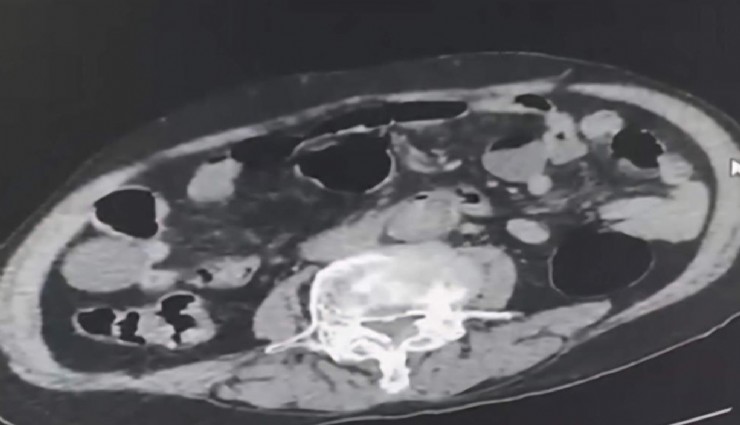

Denizli İl Emniyet Müdürlüğü Narkotik Suçlarla Mücadele Şube Müdürlüğü ekipleri, uyuşturucu madde ticaretini önlemeye yönelik yürüttükleri çalışmalar kapsamında, şehir dışından Denizli’ye uyuşturucu getirmeye çalışan 2 yabancı uyruklu kişiyi takibe aldı. Şüphelilerin, kente getirdikleri uyuşturucuyu teslim edecekleri kişiyle buluştukları sırada düzenlenen operasyonla 3 kişi gözaltına alındı. Yapılan incelemede, yabancı uyruklu zanlılardan birinin uyuşturucu maddeyi cinsel organında sakladığı ortaya çıktı. Şüphelilerin üzerlerinde ve adreslerinde gerçekleştirilen aramalarda 6 parça halinde 145 gram metamfetamin ile 260 gram sıvı sentetik ecza ele geçirildi.